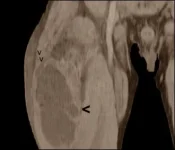

A scan showed that the inflammation had already reached deep into his muscle. The dark patch on the scan below is the liquid in the swelling.